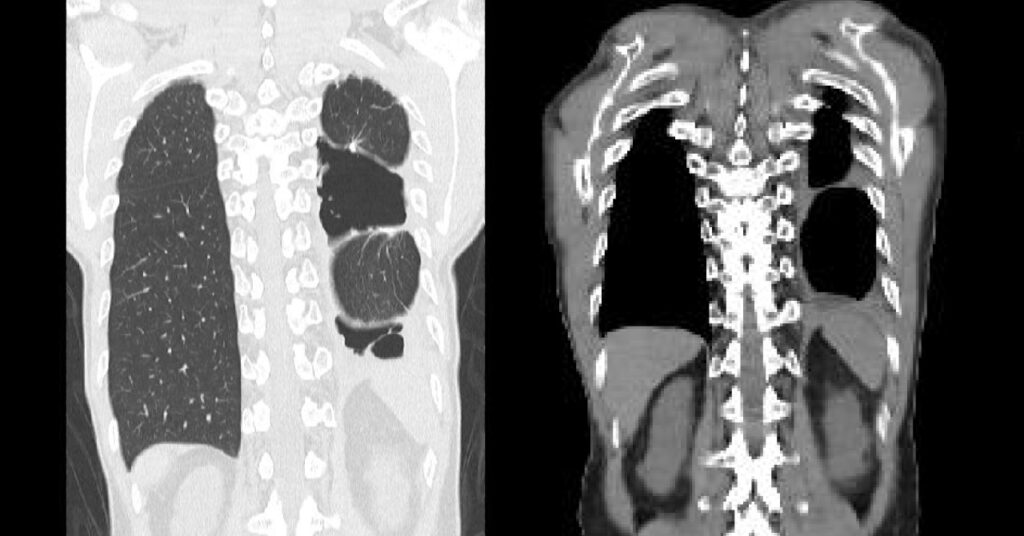

左:2024年10月1日

二度目の手術後、経過観察中に撮影された画像です。

この時期は、痛みが続きほとんど歩けませんでした。

手術の影響による含気量の低下や不均一さが見られ、肺が十分に広がっているように見えます。

右:2025年2月25日

Greeus Clinicでの治療を継続した後に撮影された画像です。

症状が落ち着き、歩行距離や体力が回復し始めた時期です。

肺の含気状態は比較的安定しており、急な悪化を示す所見は目立ちません。